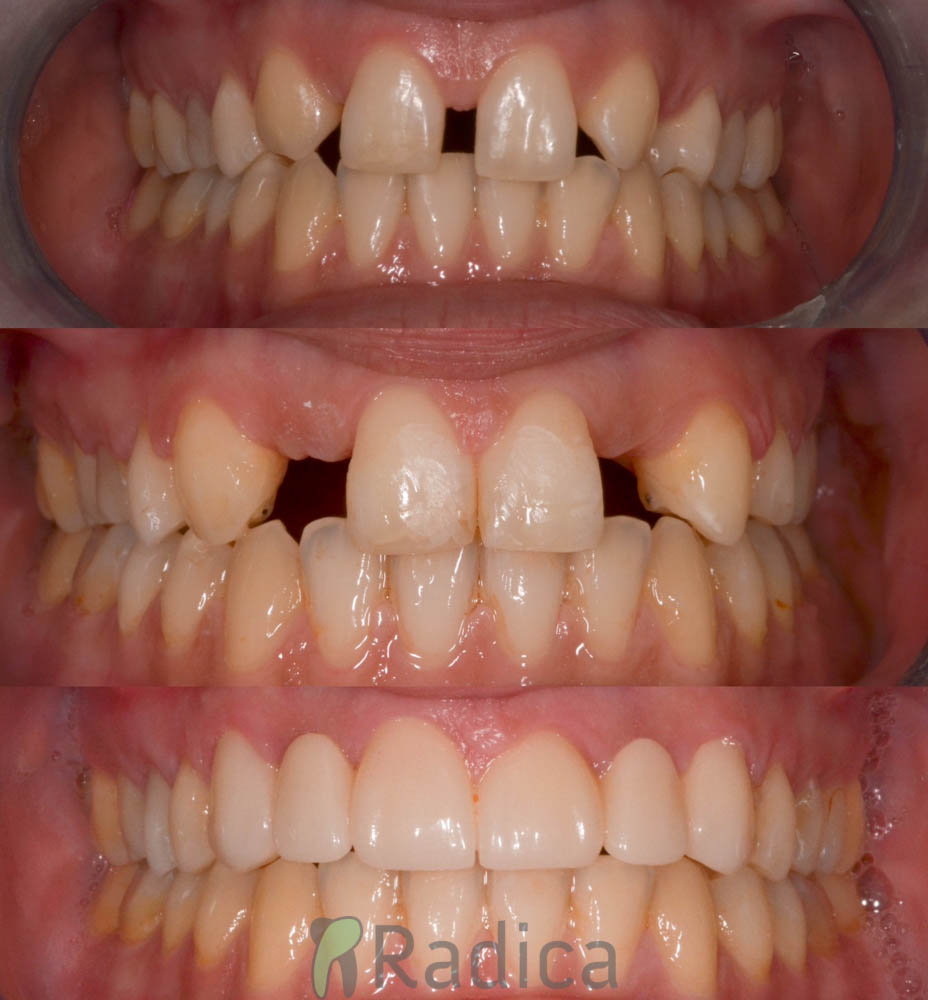

U galeriji slika su prikazani klinički slučajevi ovakvih odraslih pacijenta bilo da se radi samo o ortodontskoj terapiji ili predprotetskoj ortodonciji.